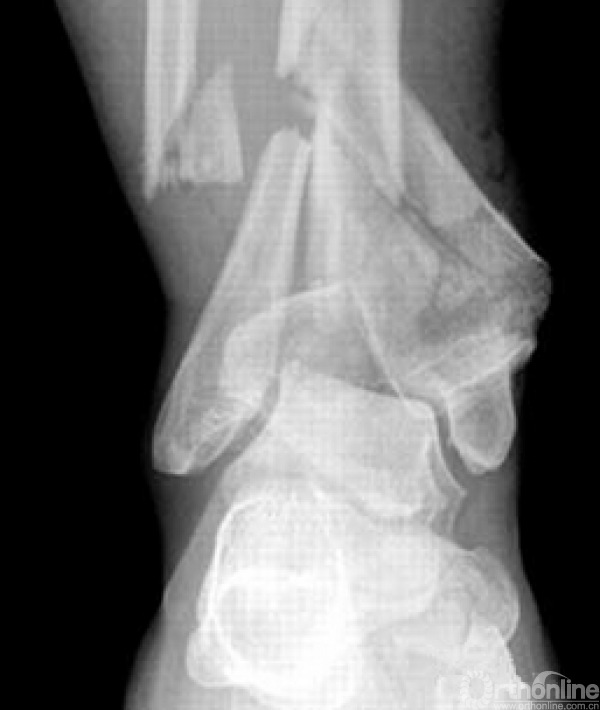

对于以下的骨折你怎么选择入路?

这样的骨折呢?